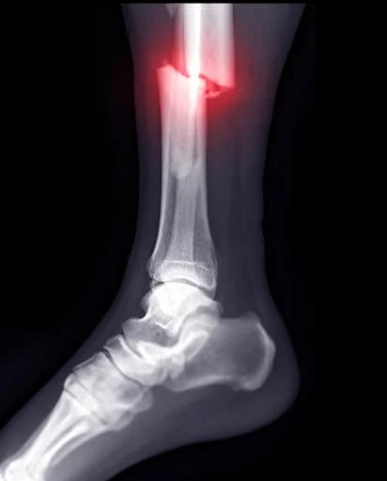

Step 4 — Medical Imaging (If Needed)

If fracture suspected → GP referral for imaging.

Important note:

Early X-rays are often negative — so we guide correct scan timing.